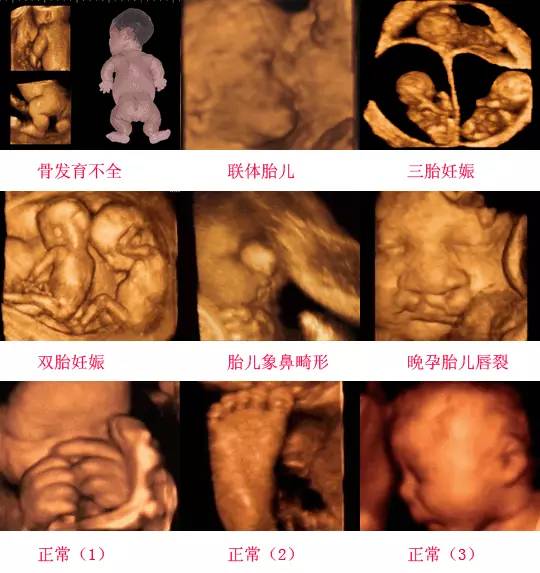

四維彩超是一種先進(jìn)的醫(yī)學(xué)影像技術(shù),通過(guò)實(shí)時(shí)觀察胎兒在母體內(nèi)的活動(dòng)情況,為醫(yī)生提供了豐富的診斷信息,在四維彩超下,我們可以清晰地觀察到胎兒的蛋蛋(睪丸)的形態(tài)、位置和大小等特征,胎兒蛋蛋是男性生殖系統(tǒng)的重要組成部分,對(duì)于胎兒的生長(zhǎng)發(fā)育具有重要意義。

在四維彩超下,胎兒蛋蛋呈現(xiàn)出特定的形態(tài)和外觀,通常情況下,胎兒蛋蛋呈現(xiàn)出圓形或橢圓形,表面光滑,內(nèi)部回聲均勻,隨著胎兒的發(fā)育,蛋蛋會(huì)逐漸增大,并呈現(xiàn)出明顯的性別特征,醫(yī)生可以通過(guò)四維彩超技術(shù),對(duì)胎兒蛋蛋的大小、形態(tài)和位置進(jìn)行評(píng)估,以判斷胎兒生殖系統(tǒng)的健康狀況。

胎兒蛋蛋的發(fā)育是一個(gè)復(fù)雜的過(guò)程,受到多種因素的影響,在胎兒發(fā)育的早期階段,蛋蛋位于腹腔內(nèi),隨著胎兒的生長(zhǎng)發(fā)育,蛋蛋逐漸下降至陰囊,這個(gè)過(guò)程受到激素、遺傳和環(huán)境等多種因素的影響,在四維彩超的觀測(cè)下,我們可以實(shí)時(shí)了解胎兒蛋蛋的發(fā)育過(guò)程,及時(shí)發(fā)現(xiàn)異常情況并采取相應(yīng)的治療措施。

四維彩超技術(shù)在評(píng)估胎兒蛋蛋發(fā)育方面具有重要意義,通過(guò)四維彩超,醫(yī)生可以實(shí)時(shí)觀察胎兒蛋蛋的形態(tài)、位置和大小等特征,了解胎兒生殖系統(tǒng)的發(fā)育情況,四維彩超還可以幫助醫(yī)生發(fā)現(xiàn)可能的異常情況,如睪丸未降、睪丸囊腫等,為及時(shí)采取治療措施提供依據(jù)。